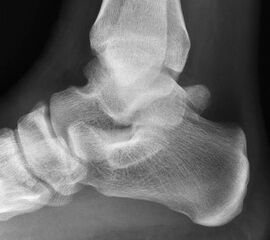

Abbildung Nr. 14-16

Reseziertes Os trigonum sowie prä- und postoperatives seitliches Röntgenbild nach arthroskopischer Entfernung eines Os trigonum.

• Bei Resektion von Osteophyten oder Entfernung eines Os trigonum postoperative seitliche Röntgenkontrolle des OSG.